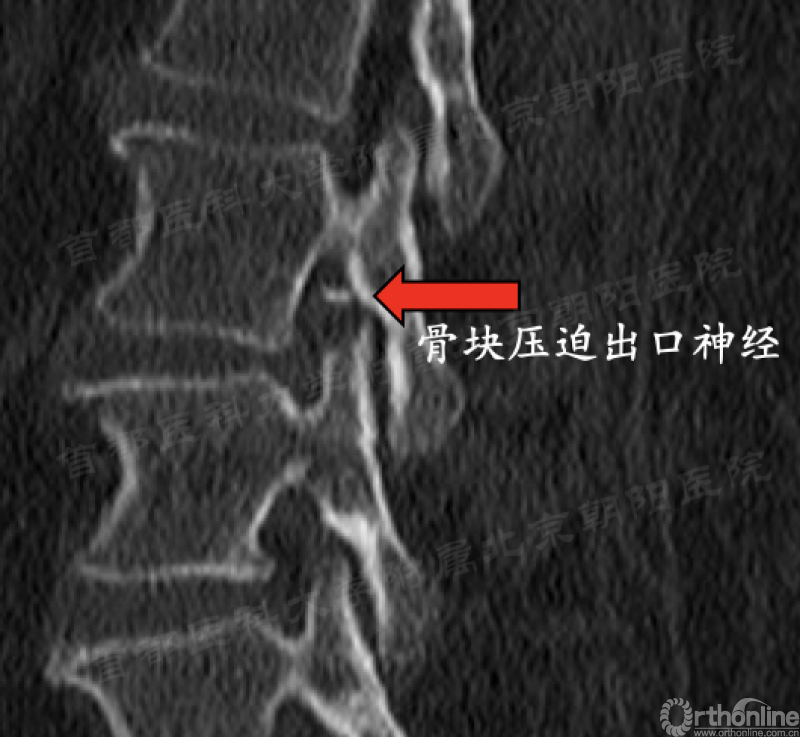

第91例,L2/3节段I-2-a区LDH。在置管后患者诉左下肢屈髋较对侧无力,无下肢放射痛及麻木,术中透视如图(红框)所示。镜下摘除髓核后将工作通道朝向背侧观察神经,患者诉颈部疼痛(脊髓高压症),镜下发现硬膜缺损(红箭头),但神经结构完整。立即结束手术。术后髂腰肌肌力IV级,大腿前方感觉减退,术后复查CT显示L3上关节成型后游离骨块导致出口神经受压。

4、在行关节突成型时应警惕尖部骨块游离挤压出口神经的可能性。